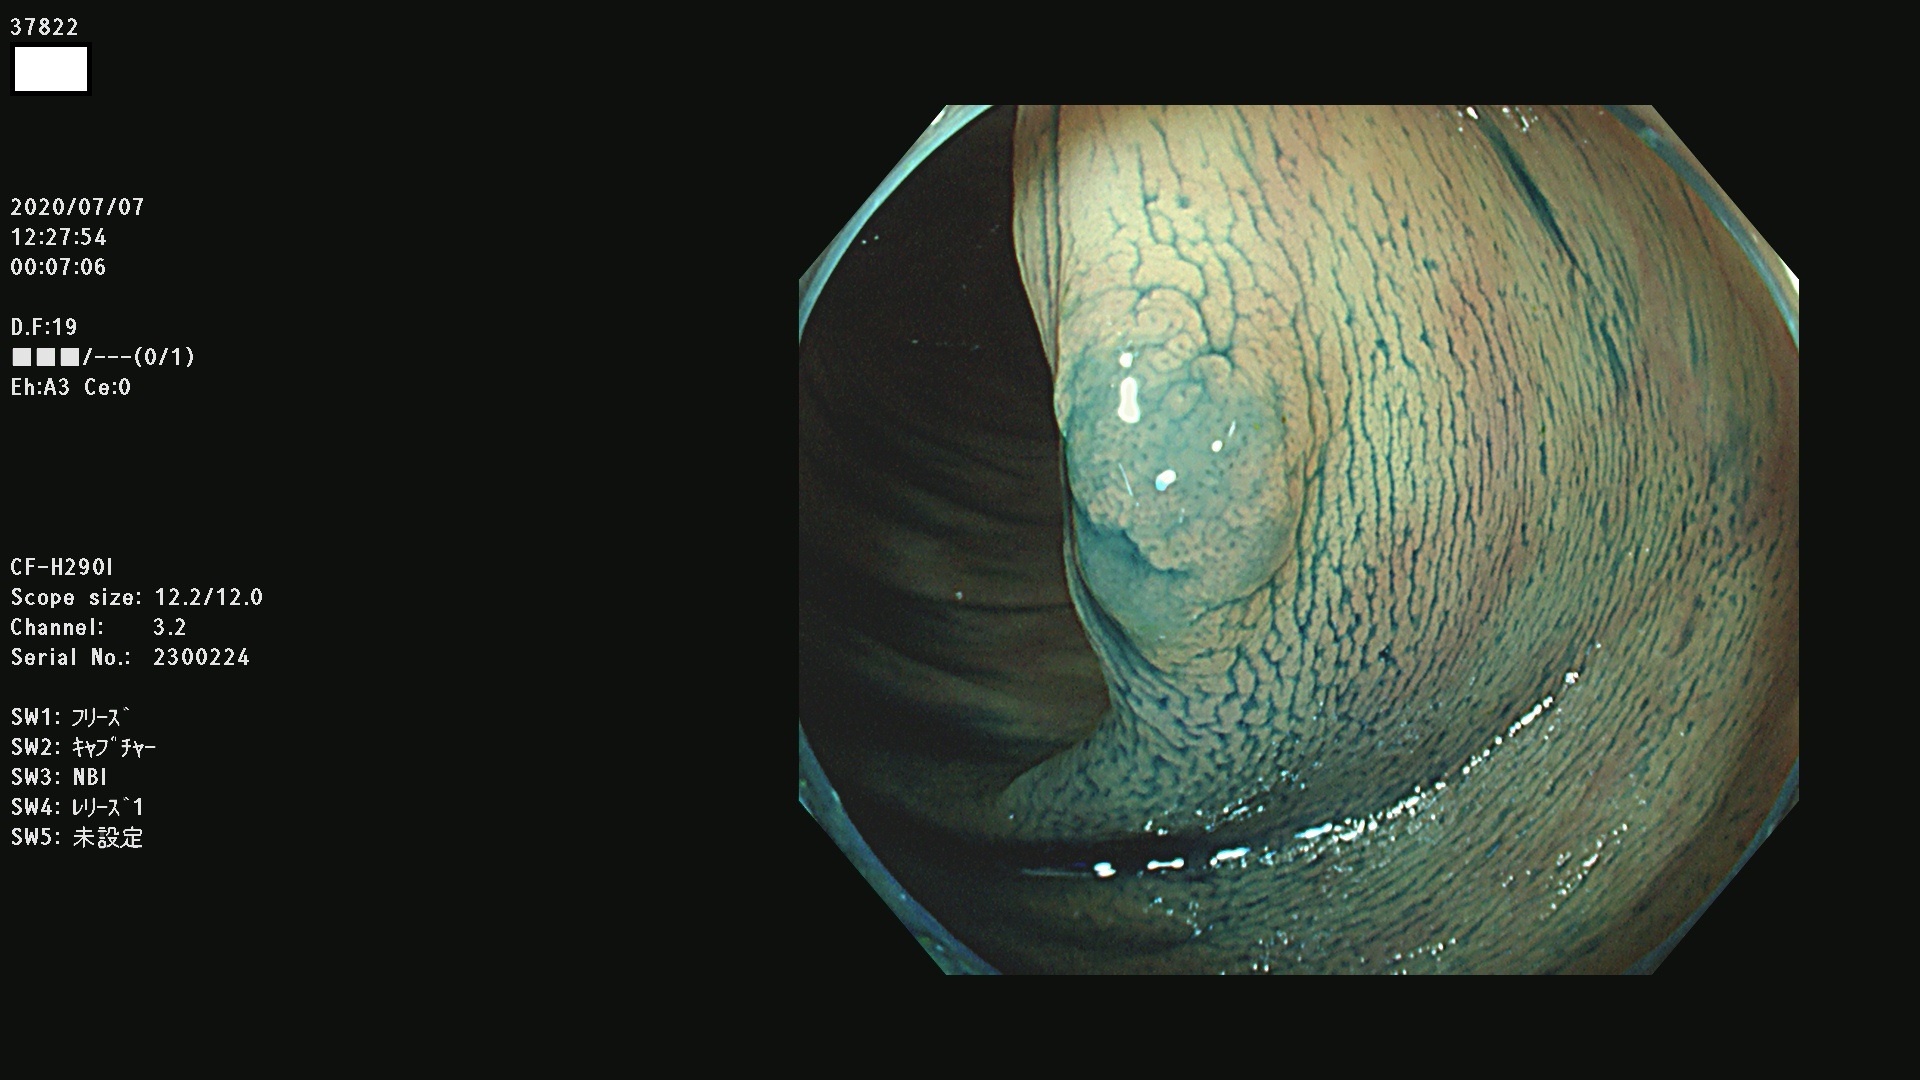

腺腫発見率 75 % (カルテ番号 37800〜37899の100名の方の検査結果で集計)大腸癌検診最新情報

以下のカルテ番号の方に腺腫(Adenoma,Group3〜5)が見つかりました(集計法)

37800(SSAPのみ) 37801 37802 37803 37804 37805 37806 37807 37808 37809(SSAPのみ) 37810 37811 37812 37813 37814 37815 37817 37818 37819 37820 37821 37822 37824 37825 37826 37827 37828 37829 37832 37833 37836 37837(SSAPのみ) 37839 37840 37842 37844 37845(SSAPのみ) 37847 37849 37850 37851 37852 37853(SSAPのみ) 37855 37856 37857 37860 37861 37862 37863 37864 37867 37868 37871 37874 37876 37877 37879 37880 37881 37882 37883 37886 37887 37888 37889 37890 37891 37892 37893 37894 37896 37897 37898 37899

発見困難で危険性の高い平坦型病変(上記100名より抽出) ![]()